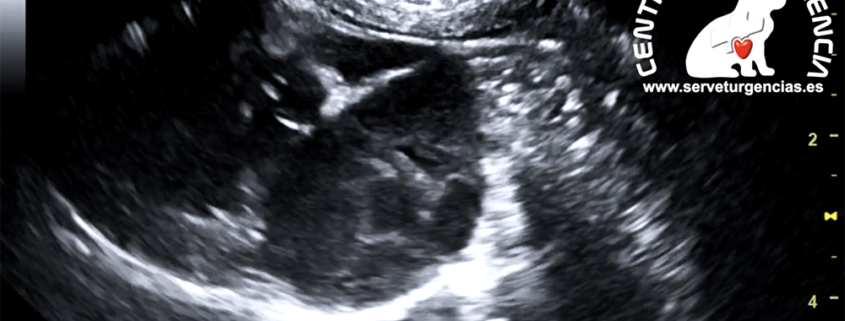

Tromboembolismo aurícula izquierda

El tromboembolismo aórtico (ATE) es un proceso por el cual se forma un trombo, típicamente en la aurícula izquierda